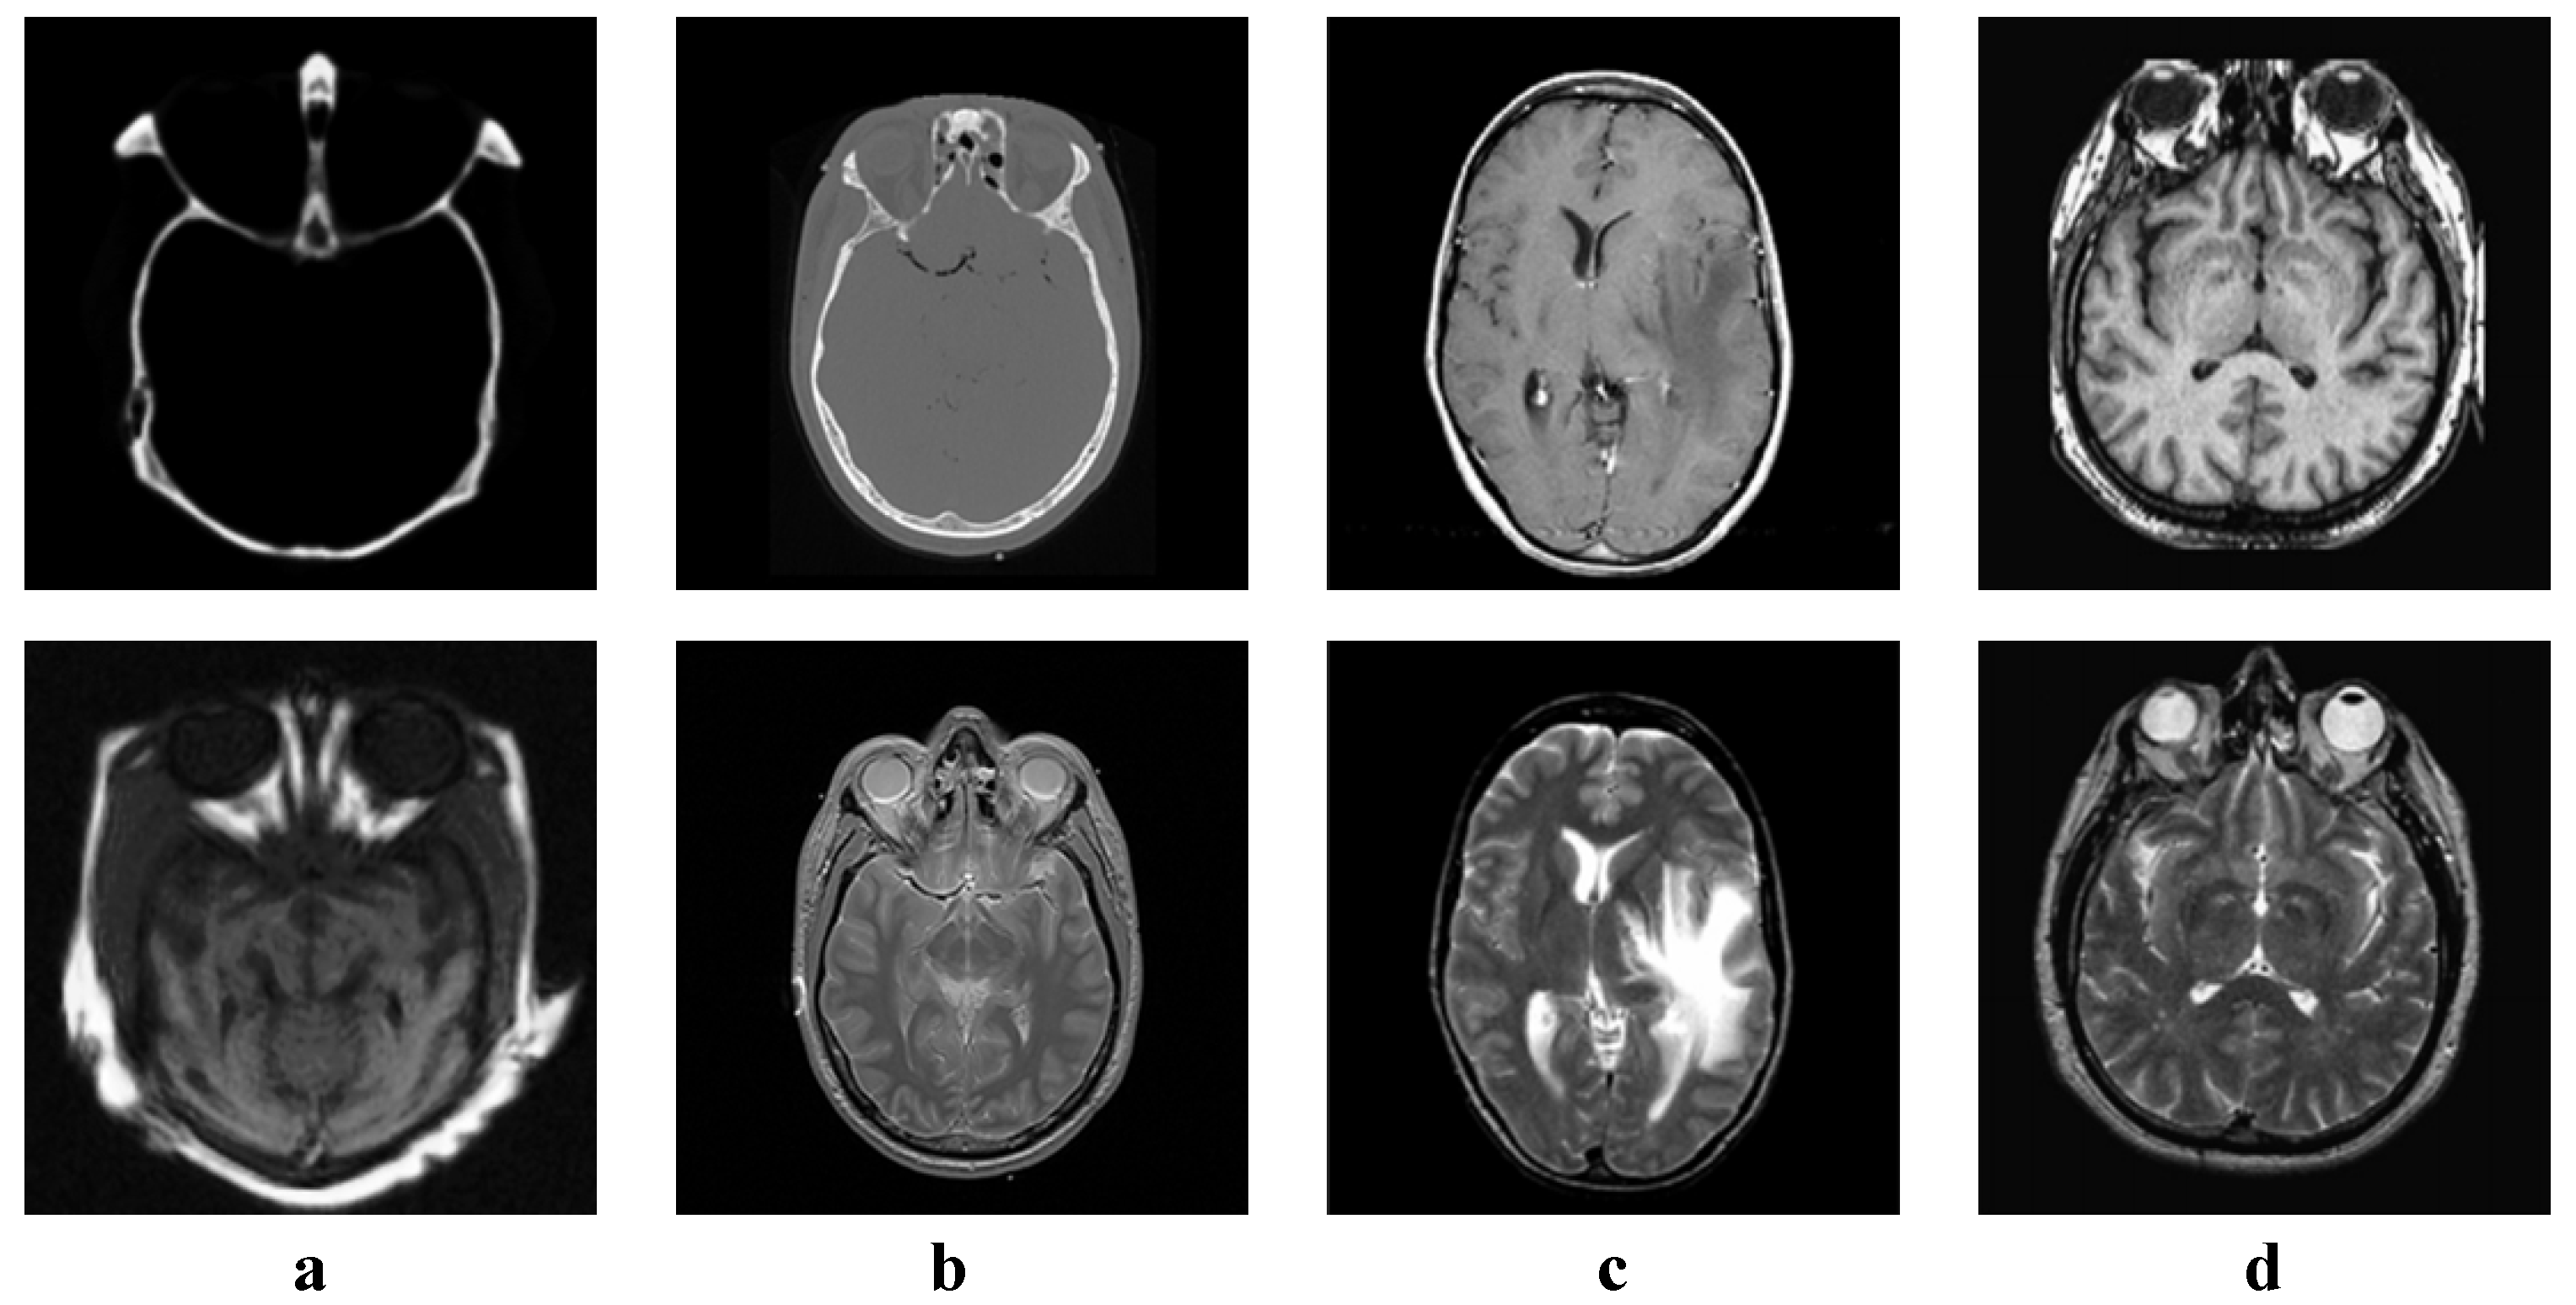

We tested all the methods using four categories of images, with four sets of source images in each category. Specifically, there are infrared-visible images shown in Figure 4, medical images shown in Figure 5, multi-focus images shown in Figure 6 and remote sensing images shown in Figure 7. The images we used for our experiments are downloadable from the following website: https://sites.google.com/view/durgaprasadbavirisetti/datasets.

Figure 5. Medical image sets. (ad) Four sets of medical source images.